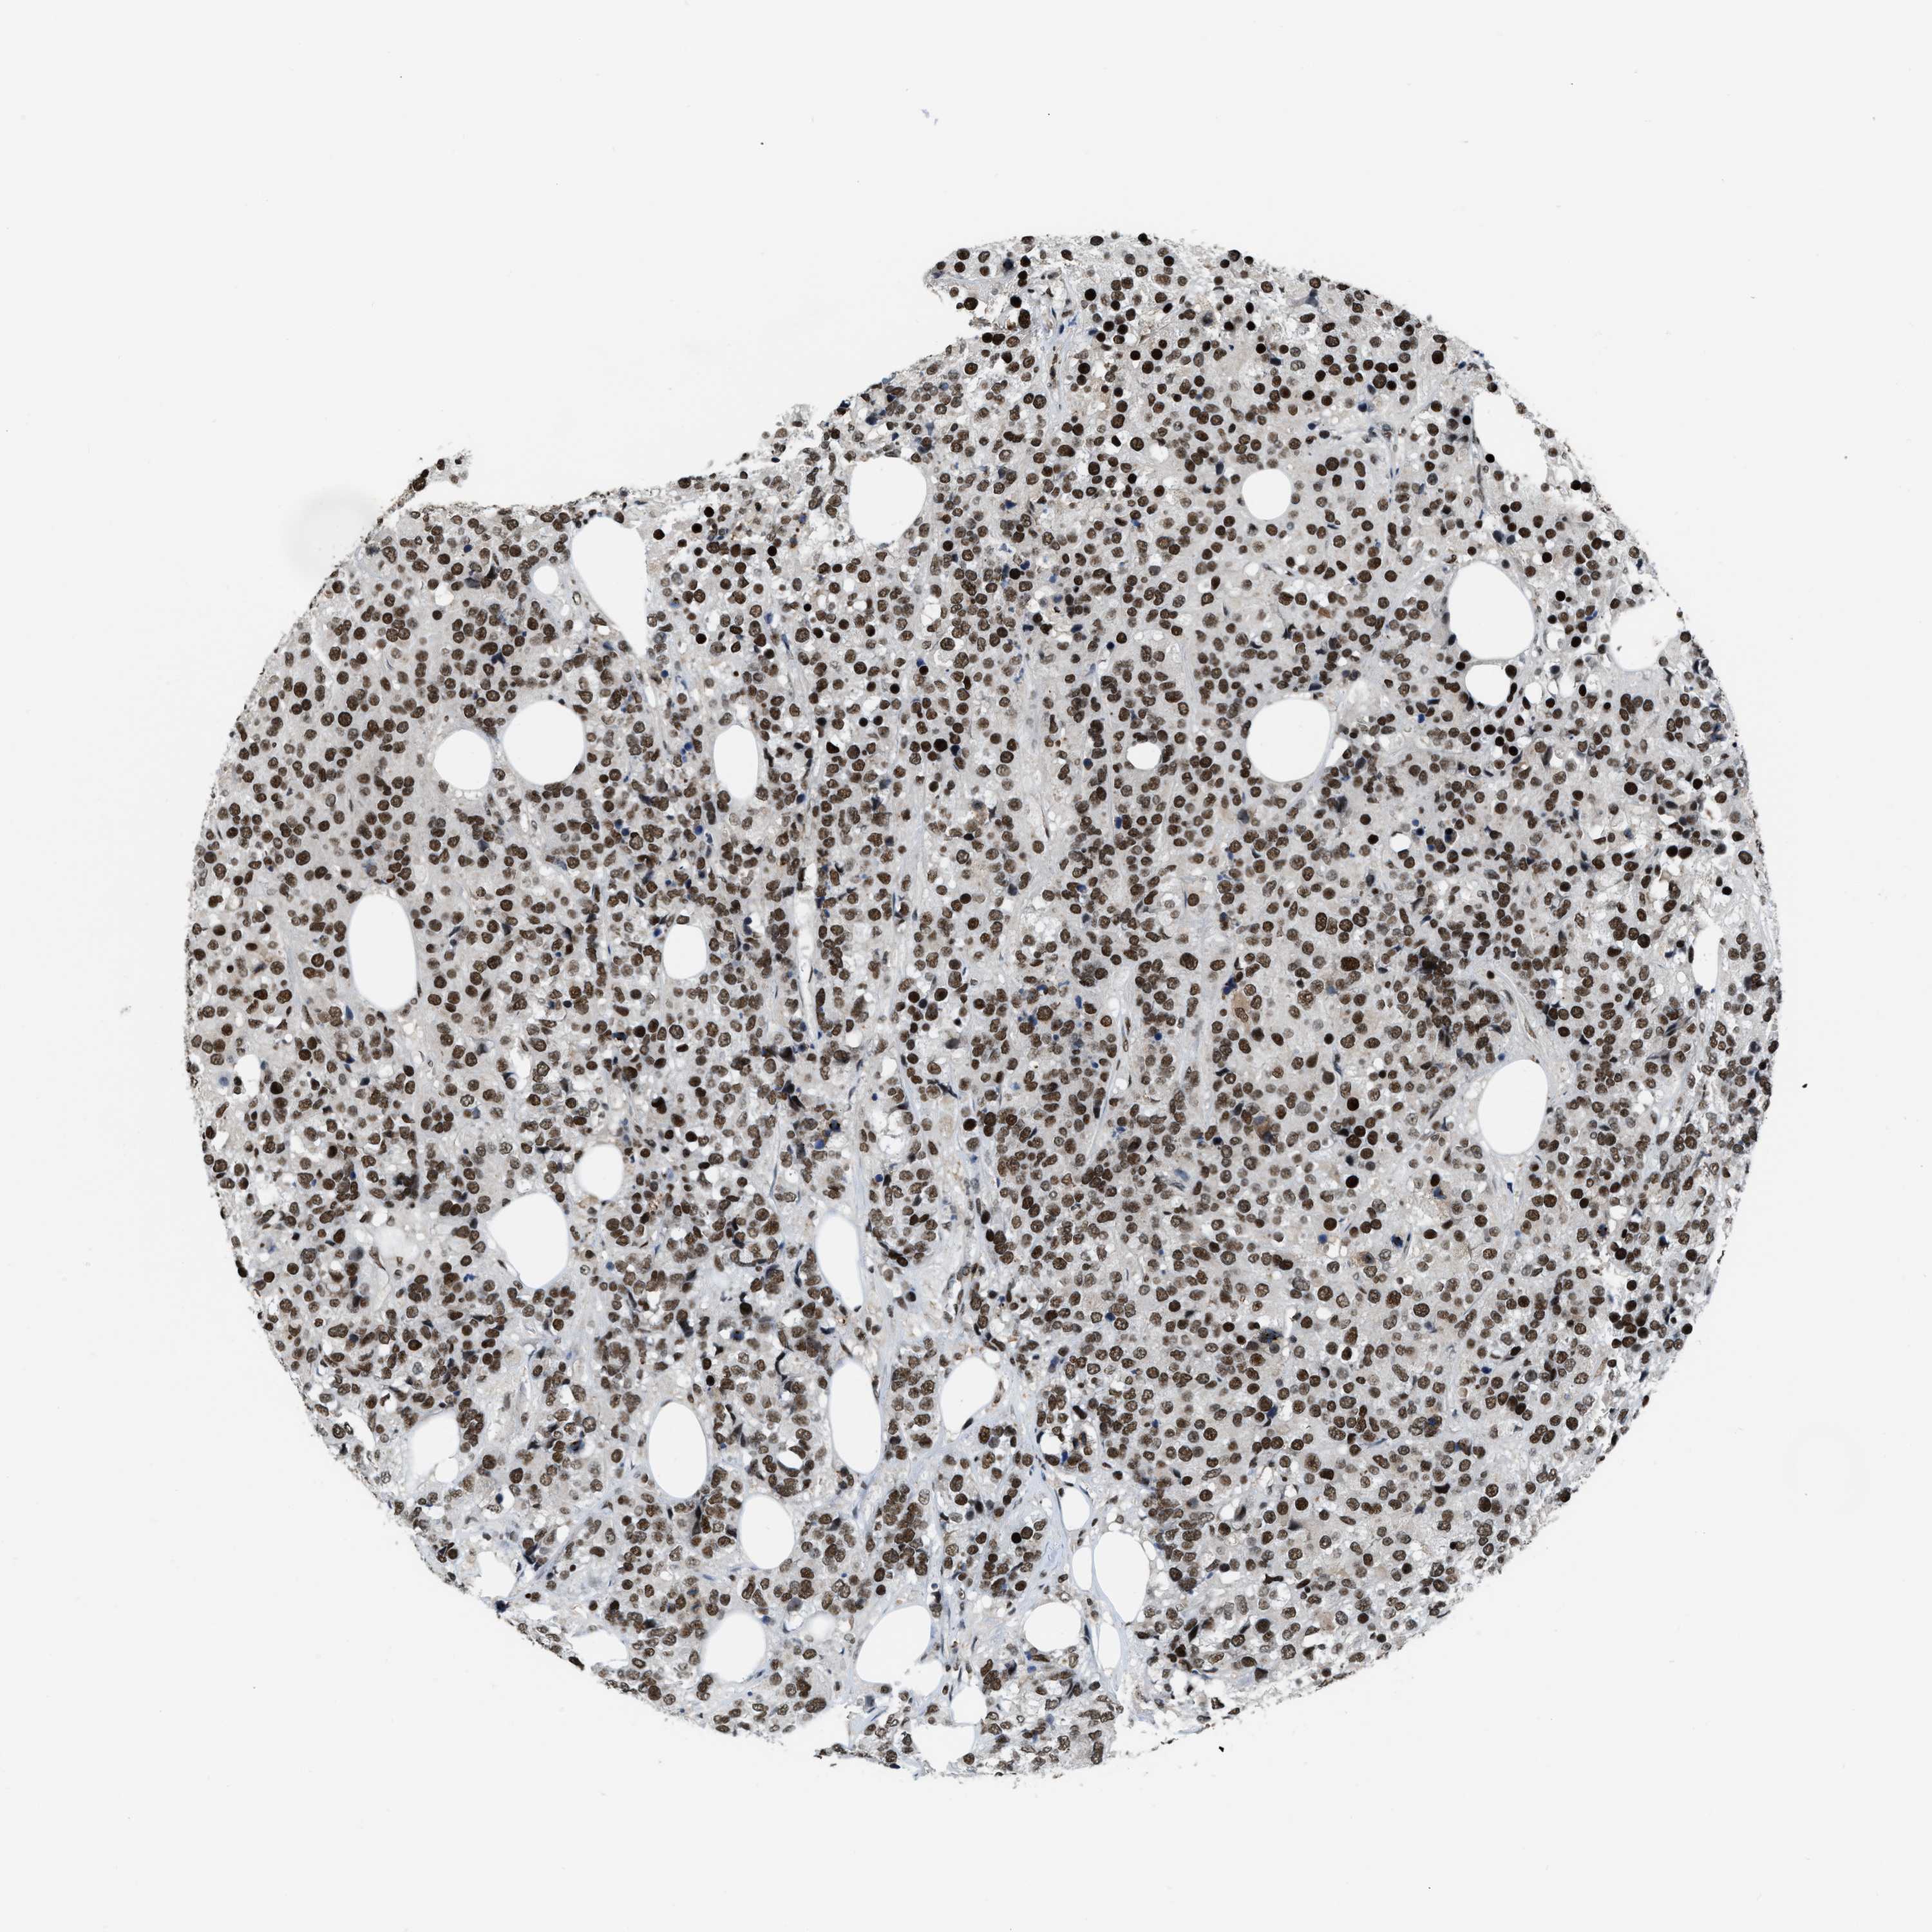

CANCER BREAST CANCER Show tissue menu

BRCA TCGA BRCA VALIDATION PROTEIN EXPRESSION

Breast cancer

Human cancer